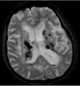

Multifocal intracranial lesions